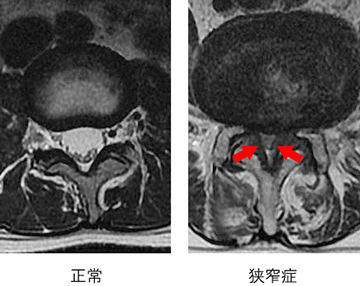

神経の圧迫の程度がわかります。狭窄症では神経の通り道が狭くなります。